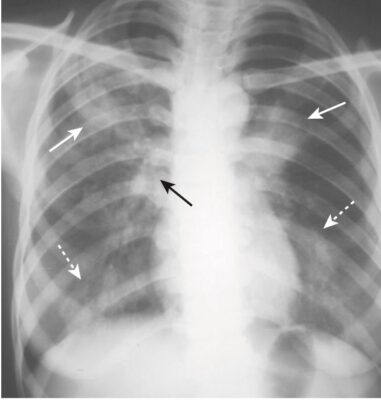

Bệnh lao phổi tiên phát (Primary Pulmonary Tuberculosis)

- Tương đối ít bệnh nhân lao tiên phát có biểu hiện bệnh lý lâm sàng. Các thùy trên bị ảnh hưởng nhiều hơn một chút so với các thuỳ dưới. Các biểu hiện cổ điển bao gồm viêm phổi thùy (Hình 16), đặc biệt với bệnh lý hạch kèm theo, bệnh hạch một bên rốn phổi hoặc hạch trung thất mà không có bệnh lý nhu mô (thường gặp hơn ở trẻ em), và tràn dịch màng phổi lượng nhiều và thường không có triệu chứng (phổ biến hơn ở người lớn) (Hình 17). Hiếm khi tạo hang.